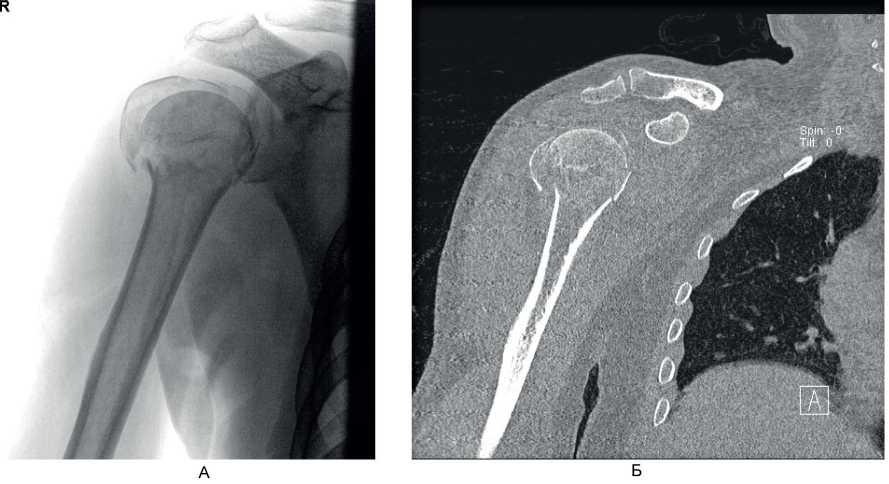

На контрольном осмотре через 6 мес у 7 (63,6 %) пациентов этой группы отмечено полное восстановление функции в плечевом суставе, у 4 (36,4 %) больных – небольшое ограничение движений и боль при движениях. Клинический пример 1. Больная М., 60 лет, поступила во ВЦЭРМ им. А.М. Никифорова в экстренном порядке. При поступлении выполнены рентгенография плечевого сустава в стандартных проекциях (рис. 6А) и компьютерная томография (см. рис. 6В). Перелом по классификации АО – В3. На 2-е сутки после поступления выполнено оперативное вмешательство – БИОС перелома хирургической шейки правой плечевой кости (см. рис. 6В).

Рис. 6. Больная М., 60 лет. А – рентгенография; Б – компьютерная томография поврежденного сегмента конечности; В – контрольная рентгенография в 1-е сутки после операции (косая проекция)